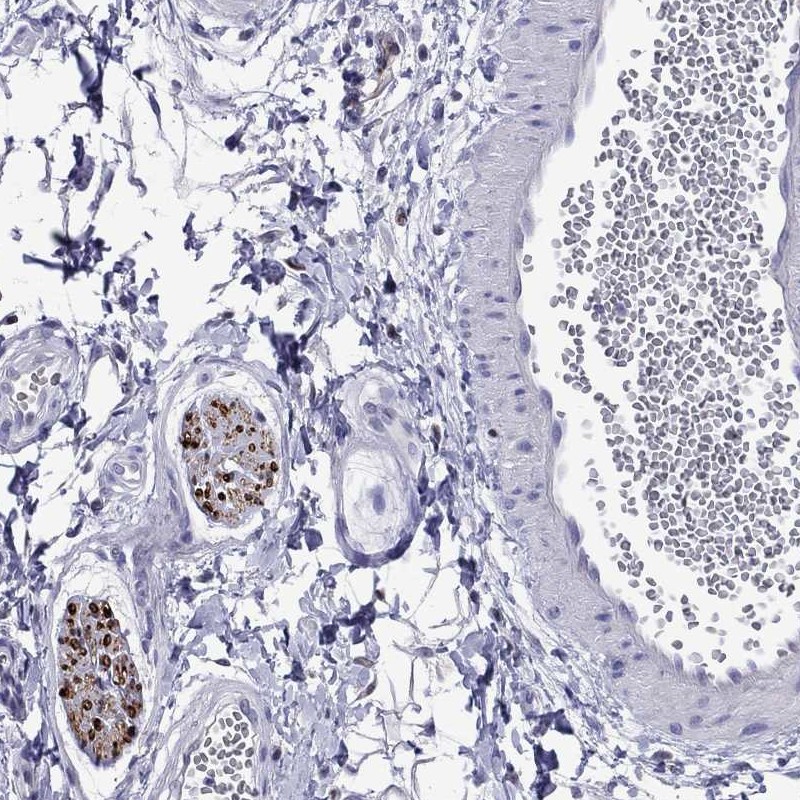

Immunohistochemical staining of human soft tissue shows strong membrane positivity in peripheral nerves.